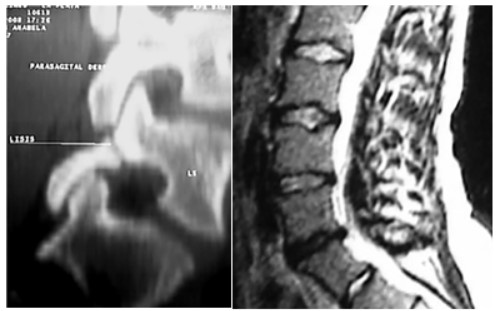

Lumbalgia

Es una sintomatología que se presenta frecuentemente en los arqueros. Cuando el dolor es persistente puede estar relacionada con discopatías o secuelas de espondilolisis o listesis (Figura 8), que aparecen con más frecuencia en los arqueros de nivel inicial e intermedio (8 a 16 años).

Figura 8. Espondilolisis y discopatía en dos arqueros